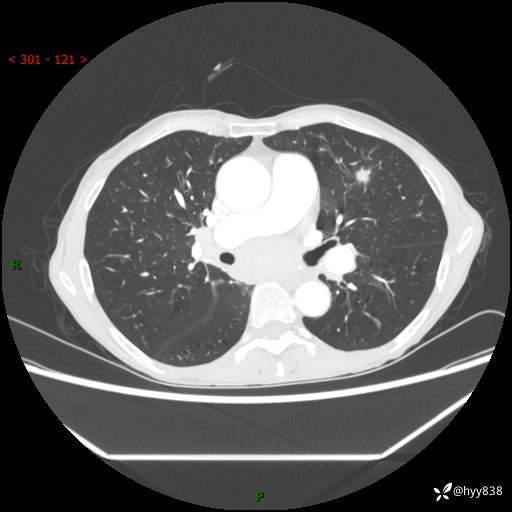

69岁/女,发现肺占位3天余。精彩好病例,请慧诊---(有结果)

【主诉】:发现肺占位3天余

【现病史及既往史】:患者3天余前因既往肺气肿复查胸部CT发现“右肺下叶结节、双肺多发结节、双肺门及纵膈淋巴结增大”,平素偶有咳白色粘液痰,下肢乏力,无明显低热、盗汗、咯血、胸痛、喘气等不适,今为求明显结节性质遂来我院门诊就诊,门诊以“孤立性肺结节”收治入院。 起病以来,患者精神饮食睡眠一般,大小便正常,体力无明细变化,体重近年来较前下降。

【检查】:胸部CT增强